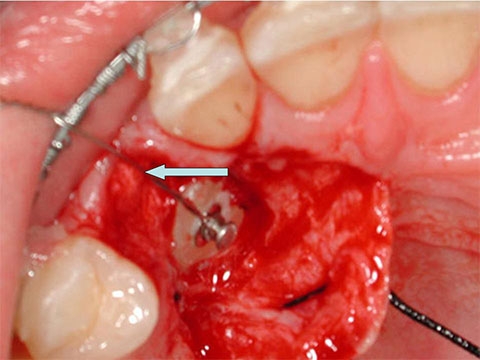

Montata l'ortodonzia,viene aperto un piccolo lembo gengivale, che mette in evidenza la posizione del canino permanente superiore destro. Il canino da latte e' gia stato estratto.

Un piccolo bottone ortodontico e' gia stato incollato, ora a questo viene fissato un sottile filo metallico.